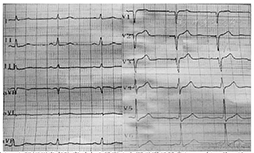

患者 男,43岁,因"反复胸前区疼痛约10 h,加重约3 h"入院。患者2014年2月5日早晨8: 00左右无明显诱因突然出现胸前区、上腹部阵发性疼痛,疼痛位置不固定,向背部放射,伴有胸闷,症状数分钟后能自行缓解,但症状反复发作,当日13: 00来我院诊治,14: 05查丙氨酸氨基转移酶(ALT) 25 U/L(正常值9~ 52 U/L)、天冬氨酸氨基转移酶(AST) 33 U/L(正常值15~ 46 U/L )、乳酸脱氢酶(LDH) 442 U/L(正常值313~ 618 U/L)、肌酸激酶(CK) 71 U/L(正常值30~ 170 U/L )、肌酸激酶同工酶(CK-MB) 20 U/L(正常值0~ 16 U/L)。患者14: 27胸痛间歇期查十二导联心电图示下侧壁导联ST段改变(图1),后患者疼痛有所好转,拟诊腹痛待查,不排除冠心病、心绞痛,给予麝香保心丸后患者离院。15: 00左右患者疼痛加重,剑突下疼痛明显,症状持续不缓解,阵发性加剧,伴有恶心、呕吐、出汗,无晕厥、心悸、呼吸困难,收入院进一步诊治。患者平素吸烟,每天约吸1包烟,否认高血压、糖尿病病史。查体:血压154/109 mmHg (1 mmHg= 0.133 kPa),两肺未闻及干、湿性啰音,心率92次/min,律齐,无杂音,腹平软,上腹部轻压痛,无反跳痛,未触及包块,肝脾肋缘下未触及,Murphy征阴性,肝肾区无叩击痛,双下肢无水肿。胸部X线片无异常。18: 25十二导联心电图无异常(图2)。18: 26查ALT 28 U/L、AST 19 U/L、LDH 433 U/L、CK 83 U/L、CK-MB 16 U/L,血糖、肾功能、血淀粉酶、凝血功能无异常。给予吸氧、严密监护、抗血小板聚集、扩张冠状动脉等处理。胸部、腹部增强CT未见胸腹部异常情况,无主动脉夹层形成。患者症状缓解不明显。22: 30查ALT 27 U/L、AST 36 U/L、LDH 431 U/L、CK 289 U/L、CK-MB 58 U/L,肌钙蛋白T 253 ng/L,血淀粉酶正常。次日0: 10十八导联心电图正常(图3, 图4)。诊断为冠心病、急性心肌梗死、心功能Killip 1级,行冠状动脉造影检查:左前降支近中段狭窄30%,对角支无狭窄;左主干无狭窄;右冠状动脉无狭窄,左回旋支近段完全闭塞;各血管间未见明显的侧支循环(图5)。手术中发现左回旋支近段严重固定狭窄并急性闭塞,予回旋支植入2枚药物支架。数天后患者病情好转出院。